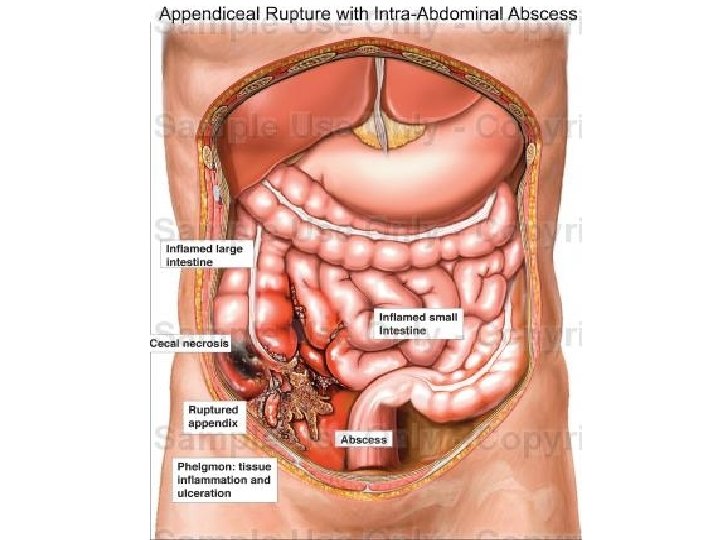

• - KOMPLIKACIONET: Appendix i gangrenizuar Perforim i appendix-it Peritonitis Abscess Sepsis

• Ne rastet e perforimit, dallohet ajer i lire poshte diafragmes.